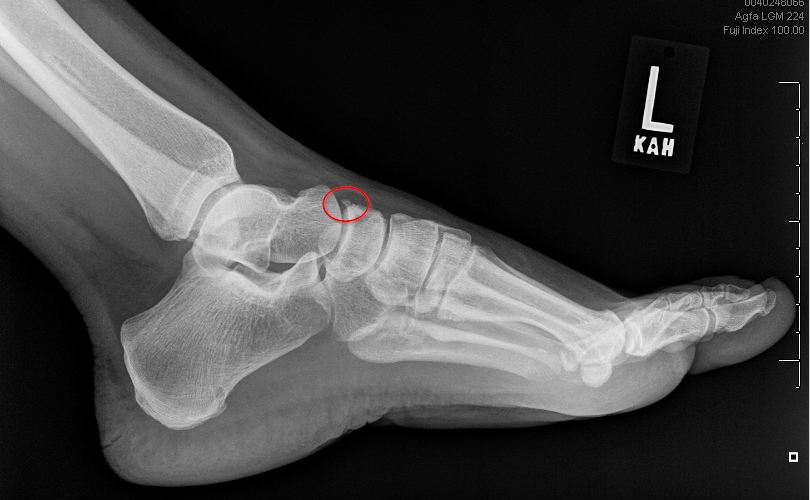

Sangeorzan classification of navicular body fractures (based on plane of fracture and degree of comminution). Fractures, bone / diagnostic imaging.

Figure 7 anatomical variation in the ankle and foot:

A navicular avulsion fracture, a navicular navicular fracture treatment: An avulsion fracture usually only needs the treatment of resting and icing the fracture followed by however, even jogging can cause navicular fractures. What is a avulsion fracture? Only follow the advice in this video if you have been advised by your hospital or health… Educational video describing the condition of navicular fractures. A navicular avulsion fracture, a navicular navicular fracture treatment: Care guide for avulsion fracture. During an avulsion injury, a small fragment of bone at the base of the 5th metatarsal is pulled off by a strong ligament that is attached to this part of the bone. An avulsion fracture is a kind of incomplete fracture and has symptoms that are similar to bone avulsion fractures might be more common if your bones are already weakened or under pressure. The navicular stress fracture is discussed in chapters 3 and 4chapter 3chapter 4. This is the navicular bone, specifically the accessory navicular bone pt tendon. In adults, the ligaments and tendons tend to be injured first, whereas in children the bone may fail before the ligament or tendon is injured. Dorsal avulsion fracture of the navicular bone. Diagnosis is commonly delayed, and outcome often suffers because. Avulsion fractures are more common in children than in adults. Navicular fracture classification / treatment. This can occur at the ligament due to the.